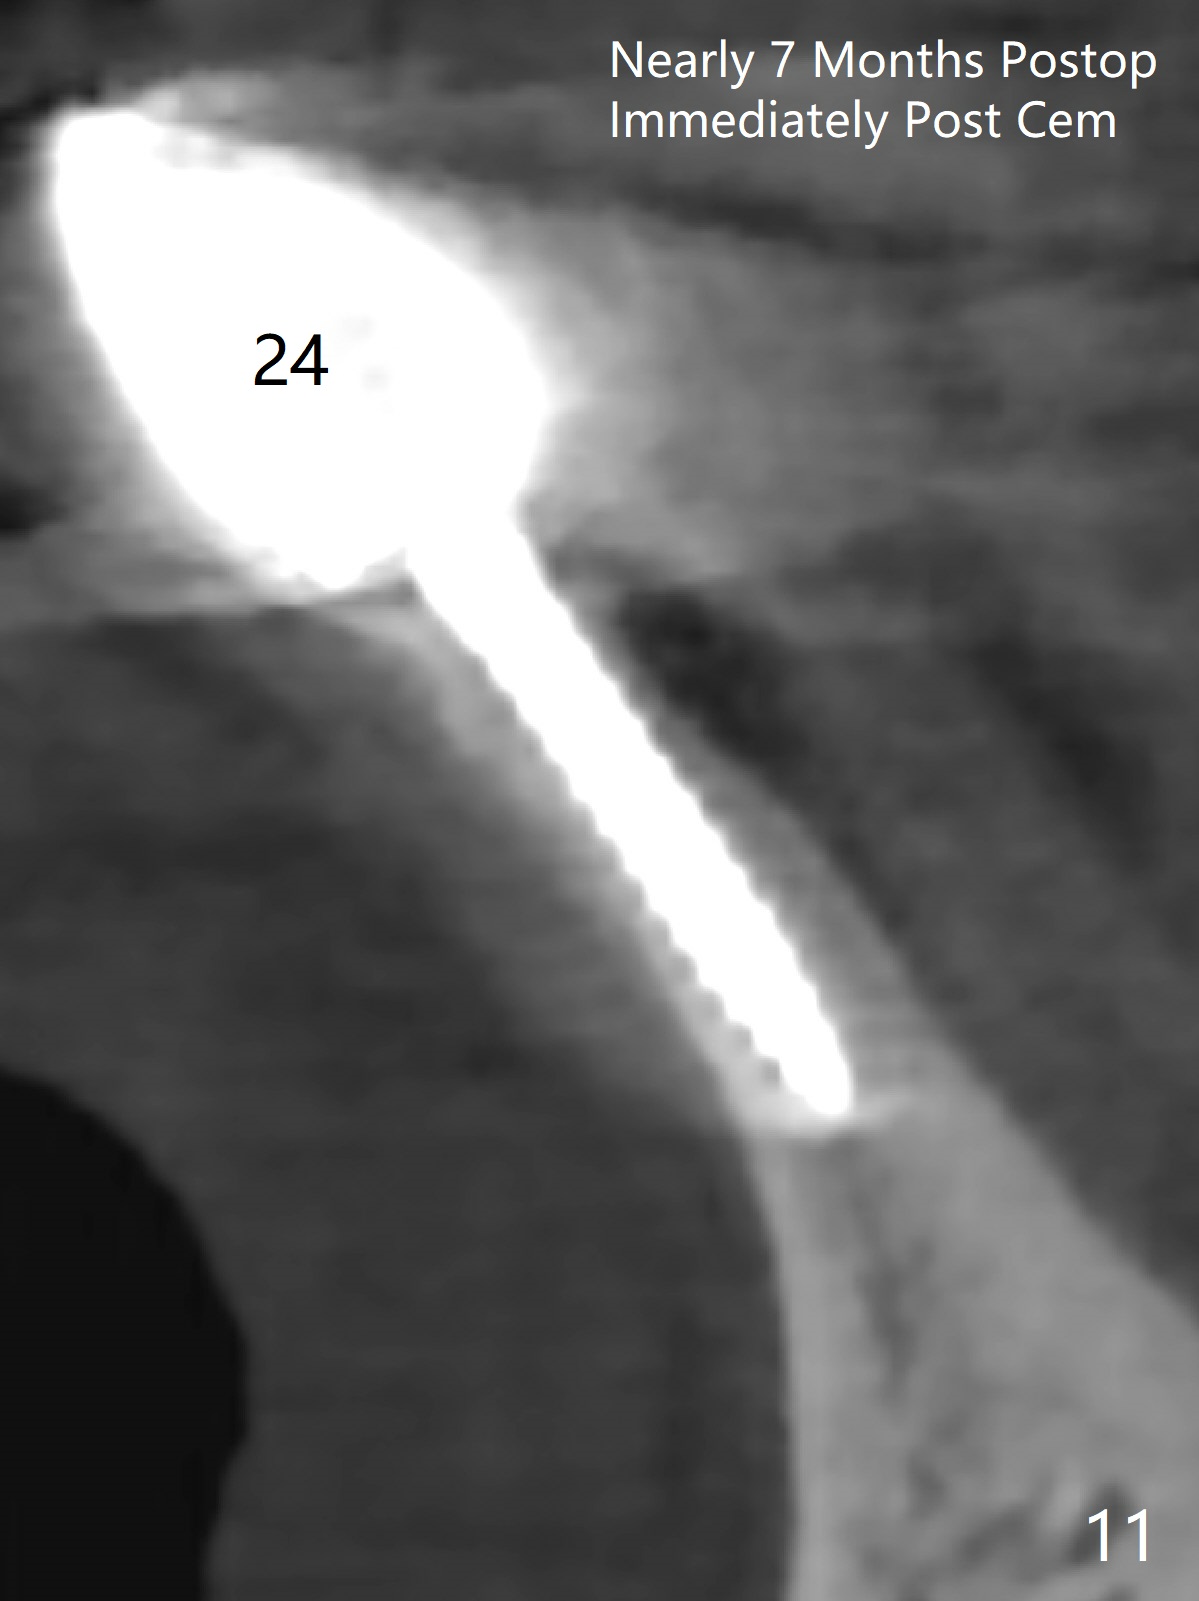

When the patient returns, the tooth #24 has exfoliated, while the ones at #25 and 26 has mobility III (Fig.1). The patient requests the tooth #23 extraction (Fig.2), but not #27. After SRP and extraction, osteotomy is initiated mesial to the sockets #23,25 and 26 (Fig.3,4) with intention to place 3 1-piece implants for 3 incisor crowns (Fig.5,6). Following Vanilla graft (Fig.5 *) a splinted provisional is fabricated to close the sockets (Fig.6). Peri-implant spaces close 5.5 months postop (Fig.7). Impression is taken after reprep for margin and parallelism (Fig.8). The final restoration consists of #23 single unit crown and #24-26 3-unit FPD (Fig.9). It appears that 2.5 mm 1-piece implants are not too small for the lower incisors (Fig.10-12), especially the central one (Fig.11). There may be perforation in the apical half of the lingual plate (L in Fig.10). The patient is not pleased with the shade of the #24-26 3-unit FPD (Fig.13 (6 months post cementation)). There is metal show through the abutments (*).